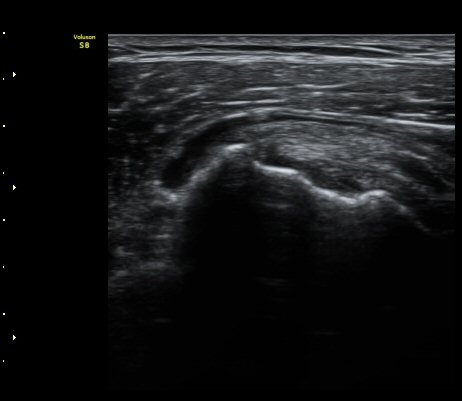

ÃÊÀ½ÆÄ °Ë»ç

2049205267_ba00cba1_IMG_20140331_2_3-c.jpg